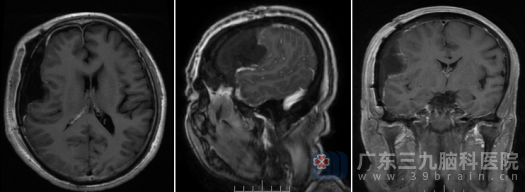

术后康复,病理定性

手术的顺利结束只是成功的一半,术后的康复同样关键。术后复查的磁共振显示,原病灶区呈切除术后改变,肿瘤已不复存在。更令人欣喜的是,陈某在术后恢复良好,出院时神志清醒,四肢活动自如,此前左上肢乏力的症状已完全消失,生活质量得到了保障。

最终的病理诊断结果为“形态学符合纤维型脑膜瘤,CNS WHO 1级”。这是一个良性肿瘤的诊断,意味着通过这次成功的手术切除,陈某已达到了临床治愈的效果,后续仅需定期复查即可。